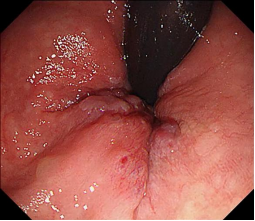

肝硬化食管和胃底静脉曲张破裂出血的内镜下组织胶注射和套扎序惯治疗

食管胃底静脉曲张内镜下套扎、组织胶治疗